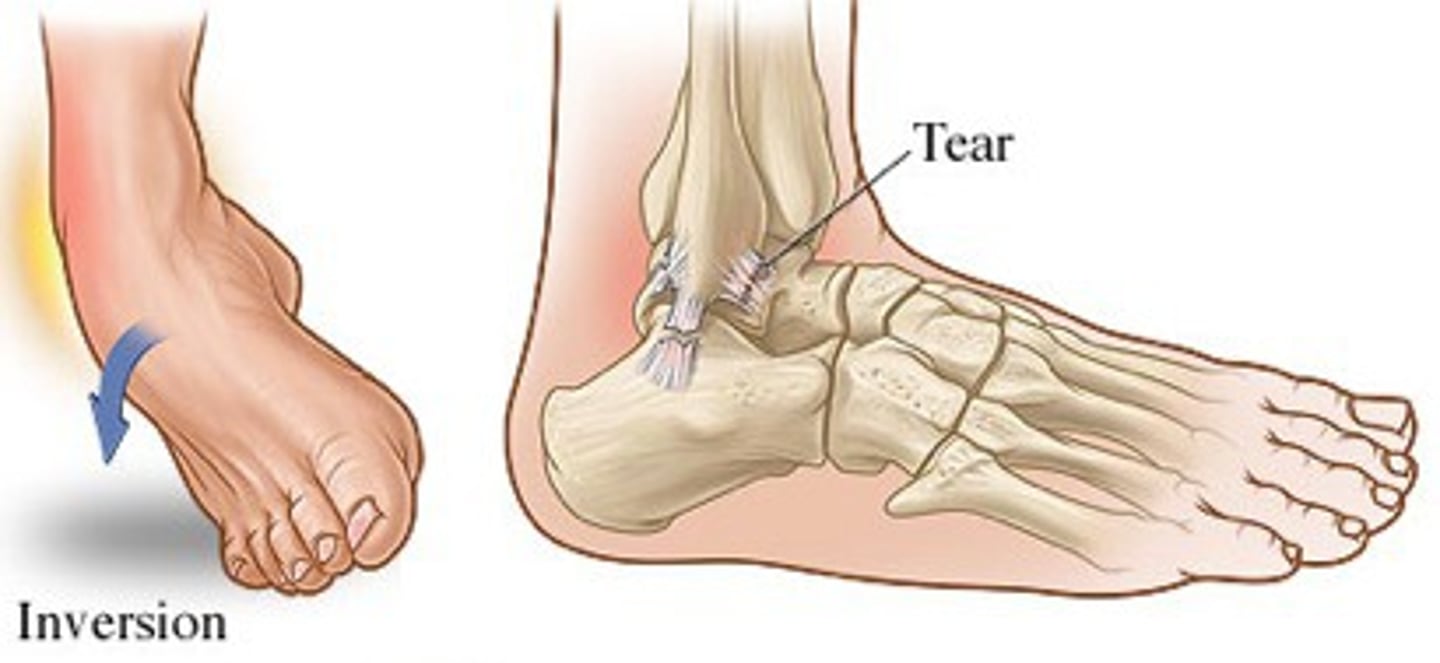

what is a common cause of ankle sprain?

inversion injury (90%)!

MC sport injury!